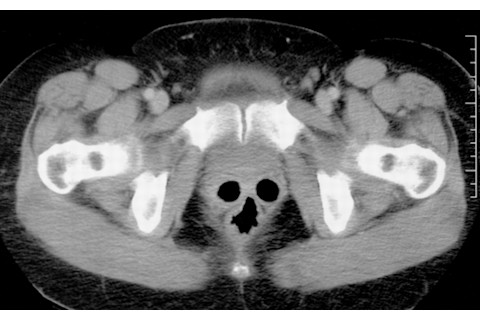

“一位45岁的男性因未降至阴囊的右睾丸而接受计算机断层扫描 (CT) 检查。超声扫描显示左侧睾丸和附睾正常。右睾丸在阴囊或右腹股沟区域均未见。在腹盆腔CT扫描中,右睾丸未被识别,但左侧阴囊似乎被一个尖叫的、像鬼魂一样的幻影占据(图1)。巧合的是,左侧阴囊内正常解剖结构的分布结合在一起,产生了这一图像。那么,未降至阴囊的右睾丸呢?没有找到。如果你是一颗右睾丸,你会想和那个鬼魂同处一个阴囊吗?”临床医学图像。一个内窥镜南瓜灯。

这个图代表了发表在《美国放射学杂志》上的一篇晦涩论文的全部内容。